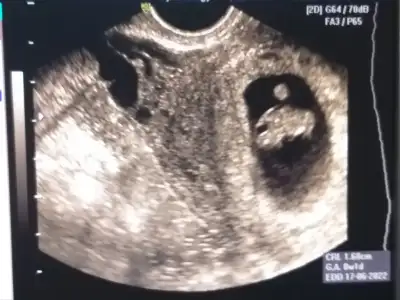

Kızçelerimm geldim geldimm iyi haberlerle çok şükür🙏🏻🙏🏻 Bebişimm çokk iyi tekme atıyordu sıpaa 😍 ama plasenta tam rahim ağzında olduğu için kanamam olmuş yarın akşam proluton iğne yaptırcam boll istirahat edicem hiçç bir sorunnyok çok şükürr 🙏🏻🙏🏻 O kadar rahatladım ki 🙏🏻 Gittiğimde yatış operasyon vs olur diye önce covid testi daha sonra damar yolu vs açtılar vallahi çok endişelenmiştim bi oh çektim şimdi🙏🏻🙏🏻❤️❤️